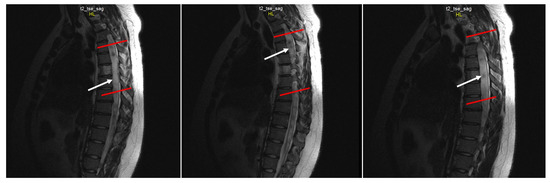

Chiari 1 Malformation (CM1) is classically defined as a caudal displacement of the cerebellar tonsils through the foramen magnum into the spinal cord. Modern imaging techniques and experimental studies disclose a different etiology for the development of CM1, but the main etiology factor [...] Read more.

Chiari 1 Malformation (CM1) is classically defined as a caudal displacement of the cerebellar tonsils through the foramen magnum into the spinal cord. Modern imaging techniques and experimental studies disclose a different etiology for the development of CM1, but the main etiology factor is a structural defect in the skull as a deformity or partial reduction, which push down the lower part of the brain and cause the cerebellum to compress into the spinal canal. CM1 is classified as a rare disease. CM1 can present with a wide variety of symptoms, also non-specific, with consequent controversies on diagnosis and surgical decision-making, particularly in asymptomatic or minimally symptomatic. Other disorders, such as syringomyelia (Syr), hydrocephalus, and craniocervical instability can be associated at the time of the diagnosis or appear secondarily. Therefore, CM1-related Syr is defined as a single or multiple fluid-filled cavities within the spinal cord and/or the bulb. A rare CM1-related disorder is syndrome of lateral amyotrophic sclerosis (ALS mimic syndrome). We present a unique clinical case of ALS mimic syndrome in a young man with CM1 and a huge singular syringomyelic cyst with a length from segment C2 to Th12. At the same time, the clinical picture showed upper hypotonic-atrophic paraparesis in the absence of motor disorders in the lower extremities. Interestingly, this patient did not have a disorder of superficial and deep types of sensitivity. This made it difficult to diagnose CM1. For a long time, the patient’s symptoms were regarded as a manifestation of ALS, as an independent neurological disease, and not as a related disorder of CM1. Surgical treatment for CM1 was not effective, but it allowed to stabilize the course of CM1-related ALS mimic syndrome over the next two years. Full article